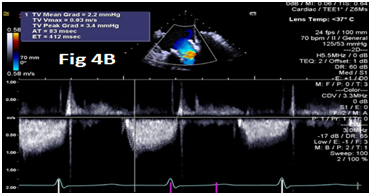

A 73-year-old female with mechanical mitral valve, tricuspid annuloplasty (32mm Edwards Physio Tricuspid incomplete ring) underwent Transcatheter Tricuspid Valve Replacement (TTVR) using off-label 29mm Edwards Sapien 3 (S3) Transcatheter Heart Valve (THV). Immediate post valve deployment, mild Perivalvular Leak (PVL) was noticed at the septal aspect (area of incomplete annuloplasty ring). Eighteen months later, patient presented with recurrent right heart failure and paracentesis due to severe tricuspid PVL (Figure 1A-C, Video 1). Percutaneous PVL closure under general anesthesia, Trans-esophageal Echocardiography (TEE) was performed. Via femoral venous access, defect was easily crossed with Agilis steerable sheath, multipurpose catheter and 0.035” glide wire. Despite recurrent attempts, wire came through the PVL but then traversed through open cells of S3 into the right ventricle (Figure 2A), confirmed with Armada 6mm balloon waist at the S3 cage (Figure 2B) (despite inflating 28mm Z med balloon inside S3 cage, Figure 2C). We decided to partially deploy the plug and assess valve function. Using 7.5F Asahi Eaucath multipurpose guide, a 12mm AmplatzerTM Vascular plug II (AVP II) was advanced through the defect. The ventricular disc was opened inside the S3 cage while body in the PVL defect (outside the S3 cage) and atrial disc on the atrial side of PVL (Figure 3A-B). With S3 function unaffected, no central leak and minimal gradient, PVL reduced to mild severity (Figure 4A-D, Video 2); the AVP II was successfully deployed (Figure 5). At 3-month follow up, there was an excellent symptomatic improvement (NYHA functional class I), with no heart failure re-hospitalization or paracentesis. Deployment of plug disc inside the valve frame is not recommended due to fear of interference with leaflet function and possible injury in long term. There was no immediate issue with the valve function in this case (due to space between the leaflet and frame of S3 and depends on size of plug used). Valve-in-Valve (S3-in-S3) would have certainly sealed all open cells treating this PVL but is more expensive option.

Figure 4 Post AmplatzerTM vascular plug II with mild residual PVL (4A), mildly elevated trans-S3 gradient (4B) and normal leaflet mobility of S3 (diastole 4C, Systole 4D).